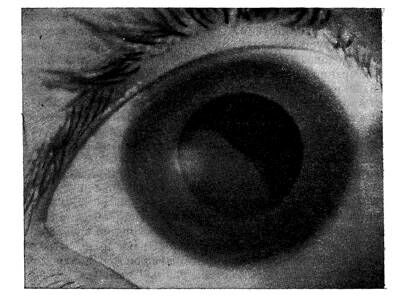

Вывих хрусталика в переднюю камеру. При полном вывихе хрусталик шарообразной формы находится в передней камере (рис.2.). обычно он прозрачный, реже частично или полностью помутневший. Передняя поверхность хрусталика прилежит к задней поверхности роговицы, задняя – к радужке, отдавливая ее сзади и прижимая зрачковый край к передней пограничной мембране стекловидного тела. Зрачок, как правило, деформирован, особенно в тех случаях, когда на отдельном участке сохранены волокна ресничного пояска, которые перекидываясь через зрачок, изменяют его форму. Зрение резко снижено.

Рис.2.

Вывих хрусталика в переднюю камеру.

При вывихе хрусталика в переднюю камеру блокируются пути оттока внутриглазной жидкости, что приводит к резкому повышению офтальмотонуса, вследствие чего появляется застойная инъекция, отек роговицы, боли в глазу, головные боли. При длительном нахождении хрусталика в передней камере развиваются дегенеративные изменения роговицы.